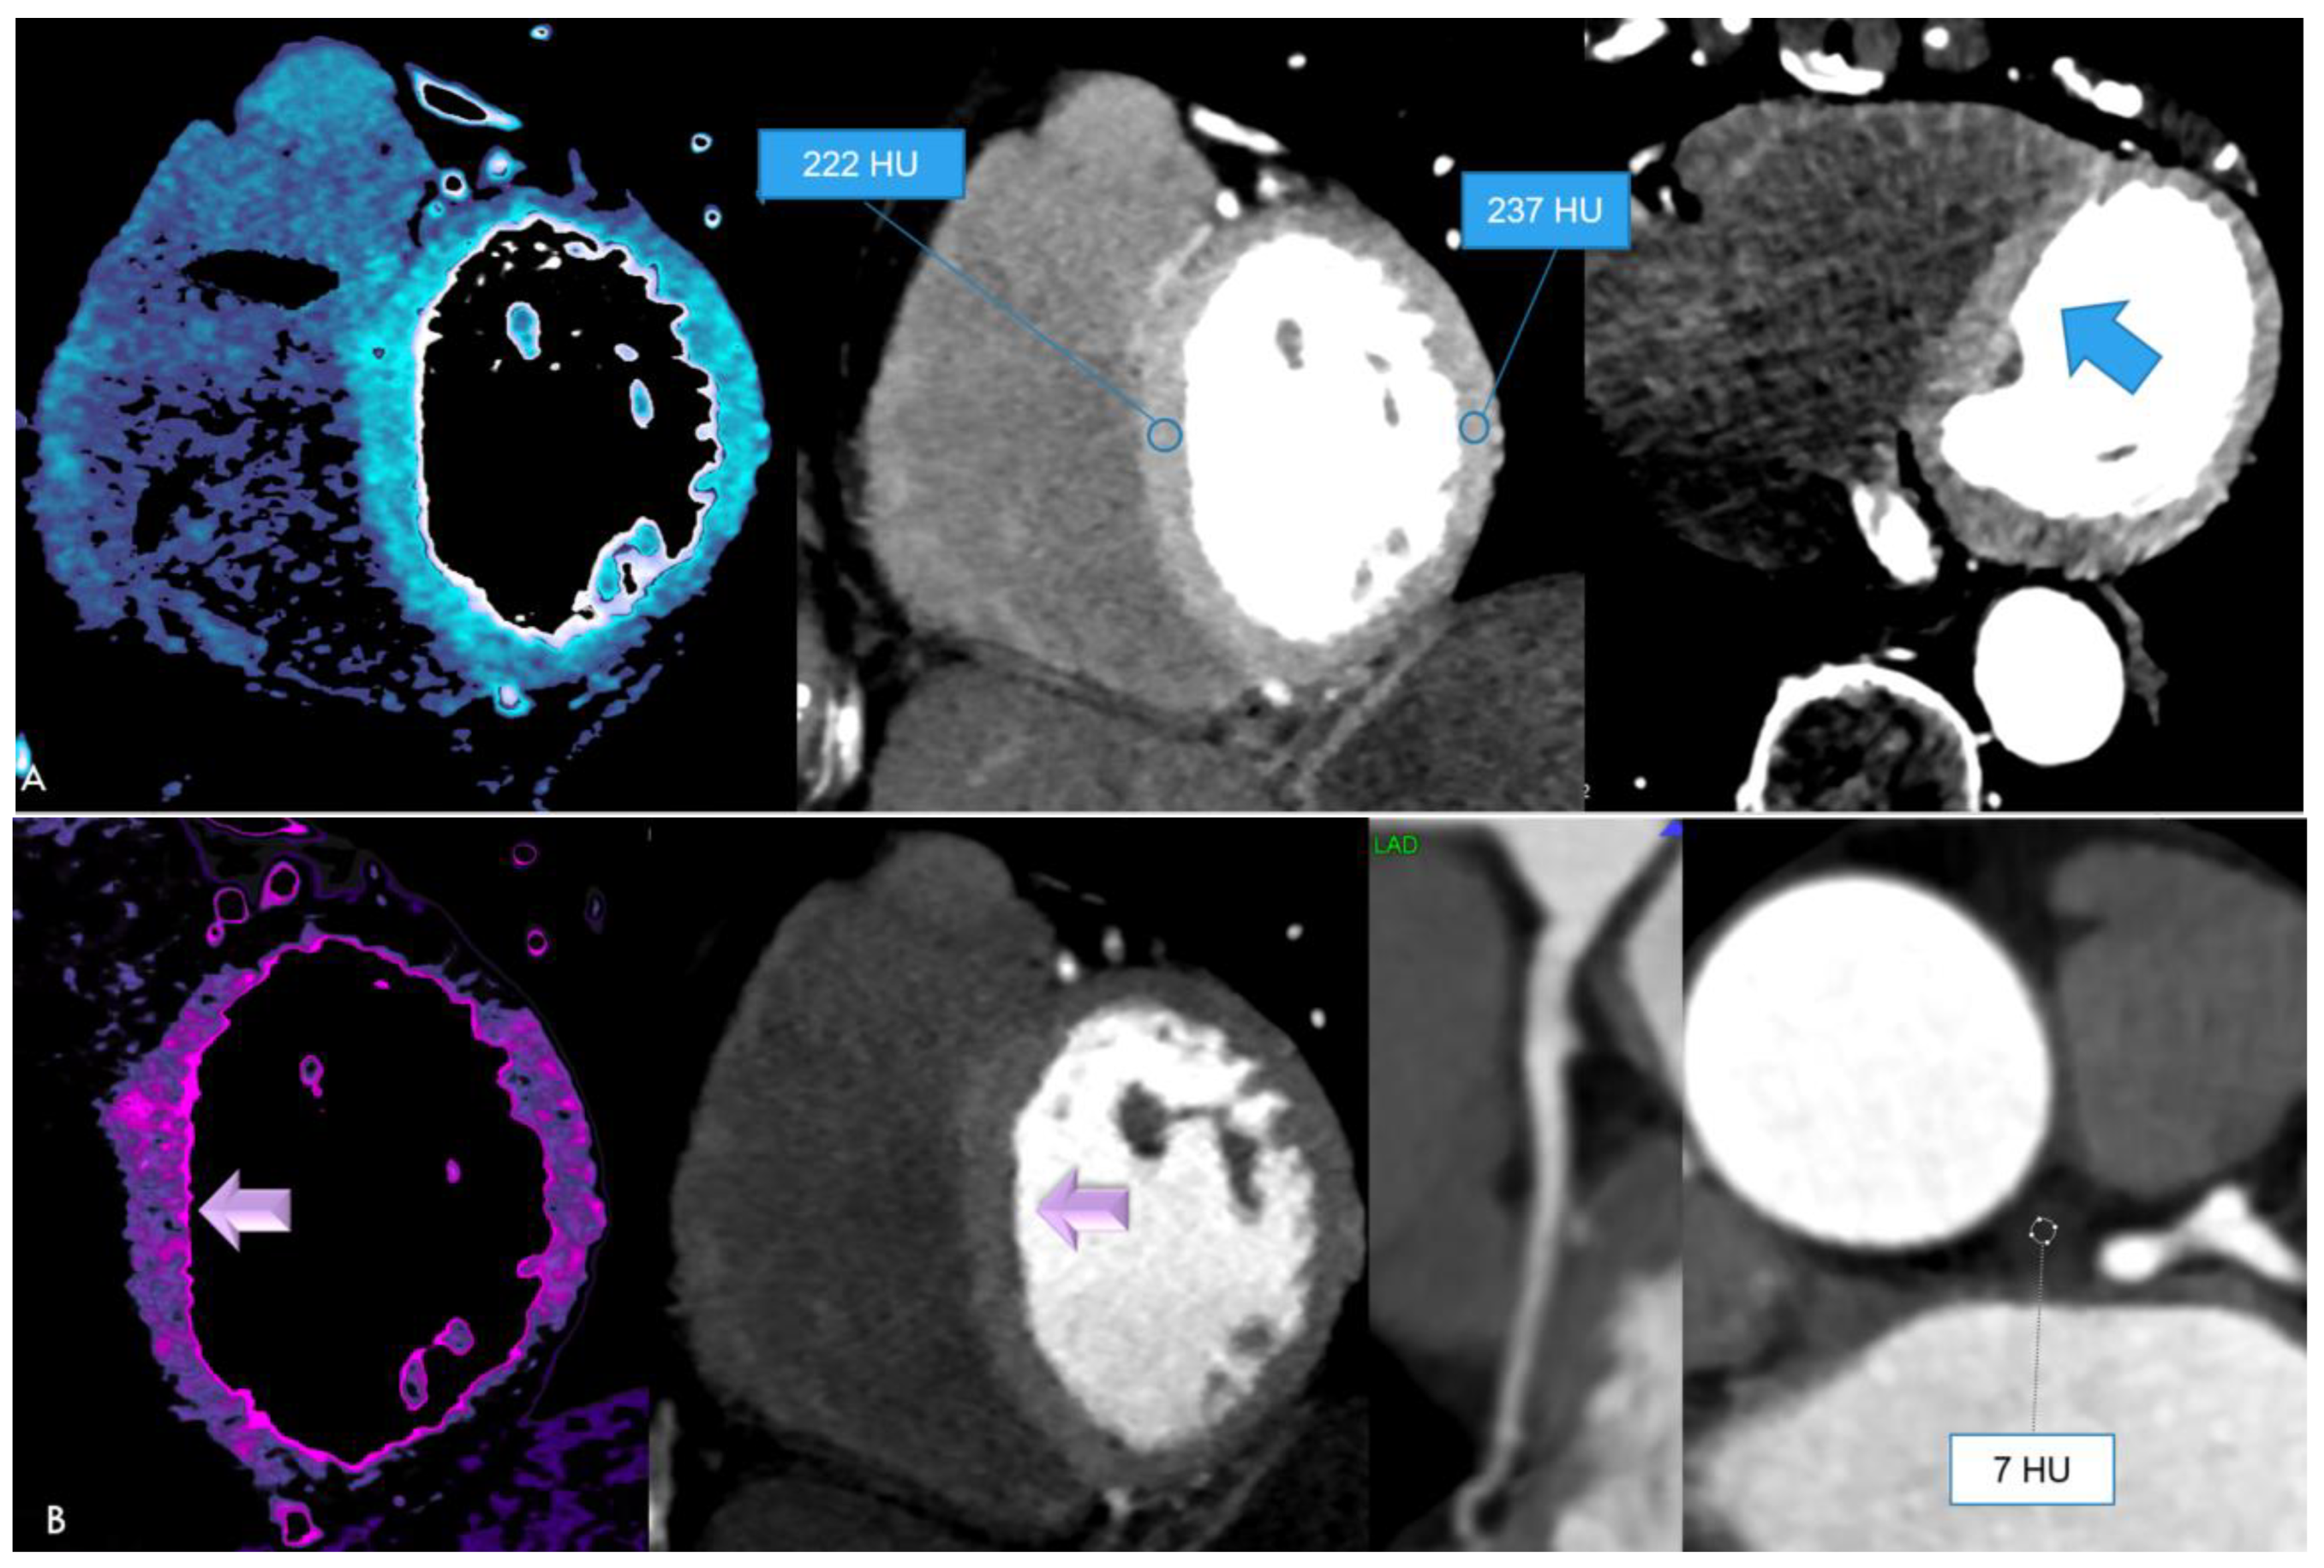

| CTA findings | ||

| Acute, unstable N = 4 | Stable N = 8 | |

| Pericardial effusion | 4 (100%) | 2 (25%) |

| Plaque rupture/ACS | 1 (25%) | 0 (0%) |

| MINOCA | 2 (50%) | 0 (0%) |

| Hyperenhancing myocardium | 1 (25%) | 0 (0%) |

| Perivascular inflammation (PCAT+) | 4 (100%) | 2 (25%) |

| Coronary artery disease by CTA | 1 (25%) | 4 (50%) |

| Nonobstructive (<50% stenosis) | 0 (0%) | 2 (25%) |

| Obstructive (>50% stenosis) | 1 (25%) | 2 (25%) |

| Diffuse vessel wall irregularities | 2 (50%) | 3 (37.5%) |

| Focal ectasia | 0 (0%) | (12.5%) |